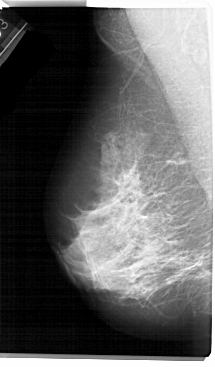

A_1305_1.LEFT_MLO

LEFT_MLO LINES 5491 PIXELS_PER_LINE 3211 BITS_PER_PIXEL 12 RESOLUTION 43.5 NON_OVERLAY